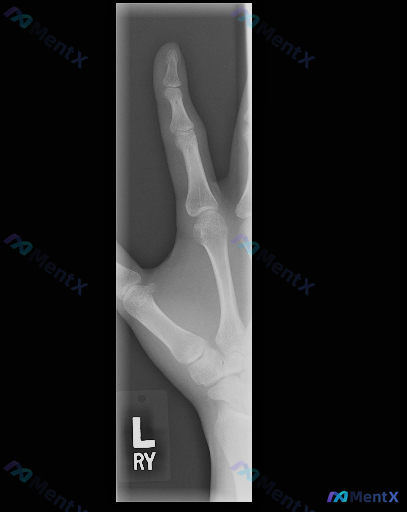

这张左手斜位X光报了"未见明显异常",但如果强调"存在异常",你会往哪查?

整理到一份左手斜位X光的影像分析资料,常规阅片结论其实是“左手中指及对应掌骨骨骼结构完整,关节间隙对位良好,未见明显外伤性骨折、退行性骨关节病或骨质破坏的影像学证据”。

但这份资料同时设定了一个反向讨论前提——假设“存在异常”,需要重新审视每一处骨皮质边缘、髓腔密度及软组织窗。

如果是你拿到这张“阴性”X光,但临床或预设要求必须找到“异常方向”,你第一眼会优先往哪几个方向考虑?